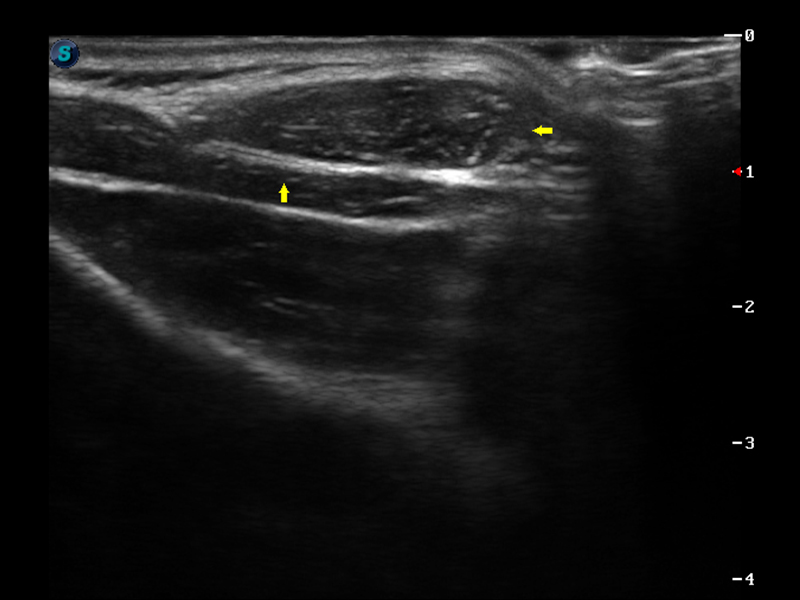

成像技术

μ-Scan微米成像